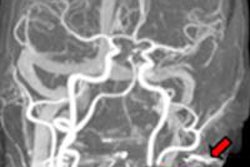

Above: ECG trace showing one-beat cardiac examination; heart rate 87 bpm. Below: Angiographic view. Bottom: Curved and short-axis views demonstrating severe stenosis on left anterior descending (LAD) artery. All images courtesy of GE Healthcare.Several studies have concluded that 64-detector-row CT delivers high diagnostic accuracy, Macron said. At the same time, as many as 15% of the coronary segments imaged at CCTA may be nonassessible, according to one report -- "and the main reasons were severe coronary calcifications and motion artifacts, the latter occurring especially with high heart rates," said Macron, a radiologist from the Centre Cardiologique du Nord who is also a consultant for GE Healthcare.